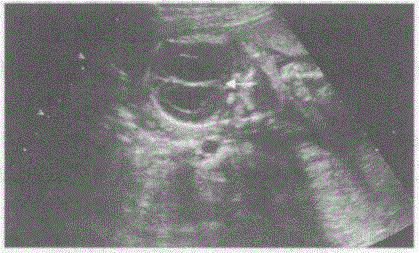

问题 临床资料:女,32岁,孕21周。 超声综合描述:颅骨未见明显扩大,双顶径与孕周相符,侧脑室扩大,内见无回声。 超声提示:

选项 A.脑积水 B.无脑儿 C.脑膜膨出 D.露脑畸形

答案 A